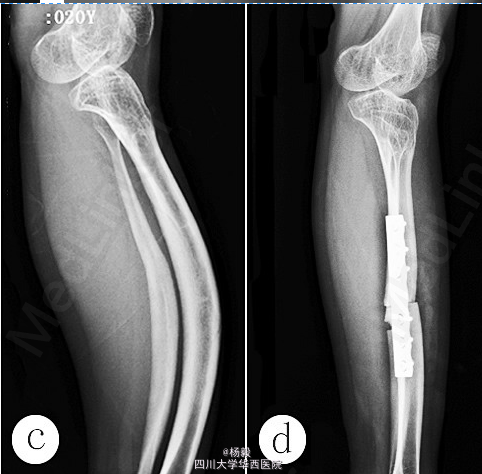

术后大、小腿切口愈合,左下肢给予石膏托外固定1个月,术后1周静脉滴注唑来膦酸5mg,4个月后股骨和胫骨截骨端愈合。2年后手术取出股骨和胫骨内固定物,术中见股骨较之前增粗,骨皮质较硬且牢固;X线片示左股骨中上段截骨和右胫骨截骨端愈合良好,骨皮质较之前增厚;再次静脉滴注唑来膦酸5mg。于2014-06-14行左胫、腓骨中段截骨矫形钢板内固定术,术中见骨质较牢固、骨皮质较厚;X线片示左股骨和胫骨骨质良好,骨皮质较之前增厚(图1d);第3次静脉滴注唑来膦酸5mg,患者双下肢基本等长。 参考文献:中国骨与关节损伤杂志2015 年4 月第30 卷第4 期Chin J Bone Joint Injury, Apr. 2015, Vol. 30, NO. 4